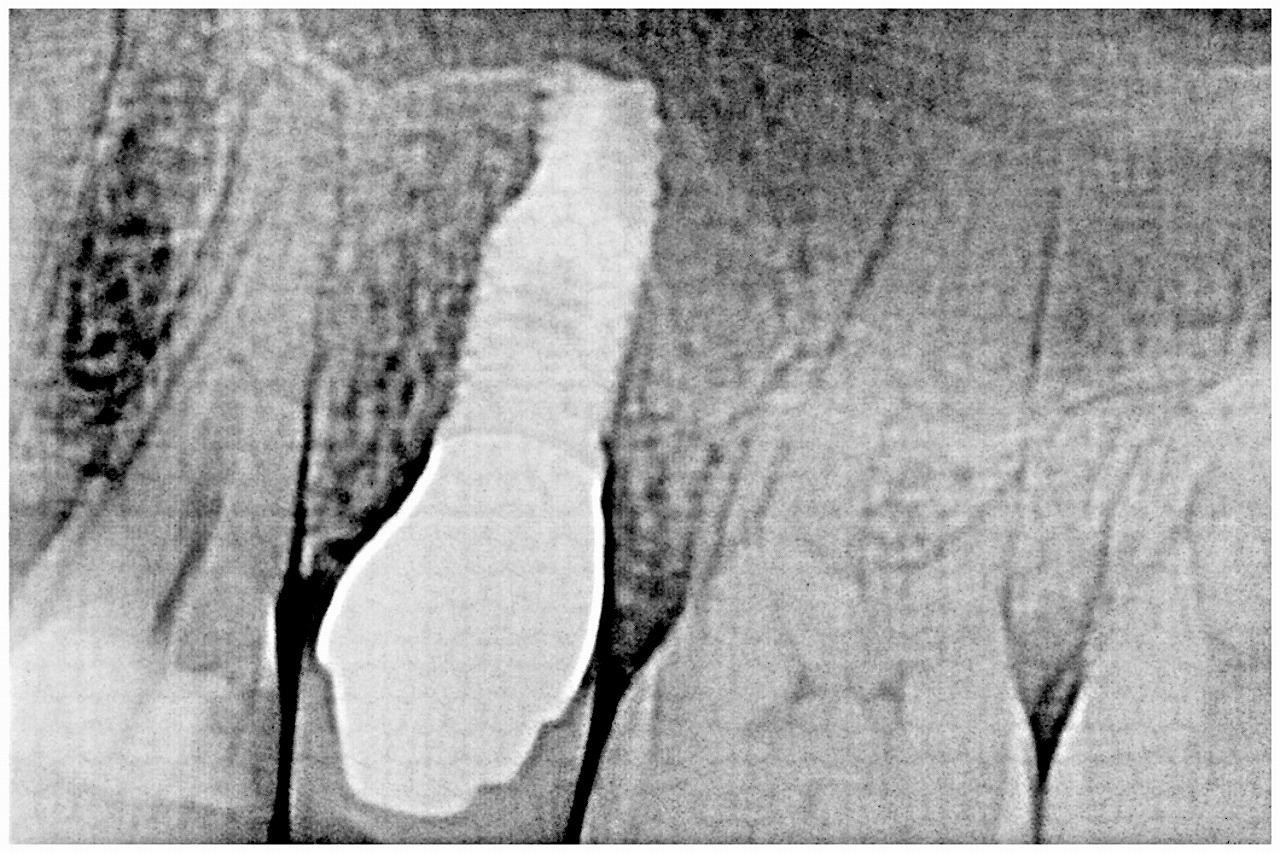

インプラント部の上部構造はこんな感じになります。| |広島市安佐南区の歯科医院 インプラント部の上部構造はこんな感じになります。 トップ お知らせ・ブログ インプラント部の上部構造はこんな感じになります。 インプラント部の上部構造はこんな感じになります。 Web診療予約 初めての方へ 選ばれ続ける理由 院内設備について 歯が痛いしみる一般歯科 歯がぐらぐらする歯周病 健康な歯を保ちたい予防歯科 子供の虫歯予防をしたい小児歯科 銀歯をセラミックに審美歯科 白い歯を目指しませんか?ホワイトニング 矯正専門医がいるので安心矯正歯科 抜けた歯を補いたいインプラント・入れ歯 医院案内 スタッフ紹介 メリィハウス歯科クリニックオフィシャルホームページ ラベンダー歯科クリニックオフィシャルホームページ お知らせ・ブログ ホーム 診療科目 一般歯科 歯周病治療 予防治療 小児歯科 審美治療 ホワイトニング 矯正歯科 入れ歯・インプラント マウスピース矯正 初めての方へ 院長・スタッフ 設備紹介 医院案内・アクセス メニューを閉じる